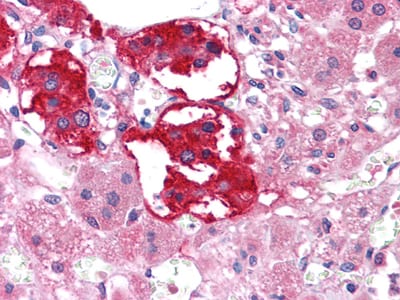

Immunohistochemical analysis of paraffin-embedded human lung squamous cell carcinoma (A), lung adenocarcinoma (B), colon carcinoma (C), breast carcinoma (D), normal sublingual gland (E), normal rectal (F), showing membrane localization with DAB staining using EphB3 mouse mAb.

Immunohistochemical analysis of paraffin-embedded human Adrenal tissues using EPHB3 mouse mAb